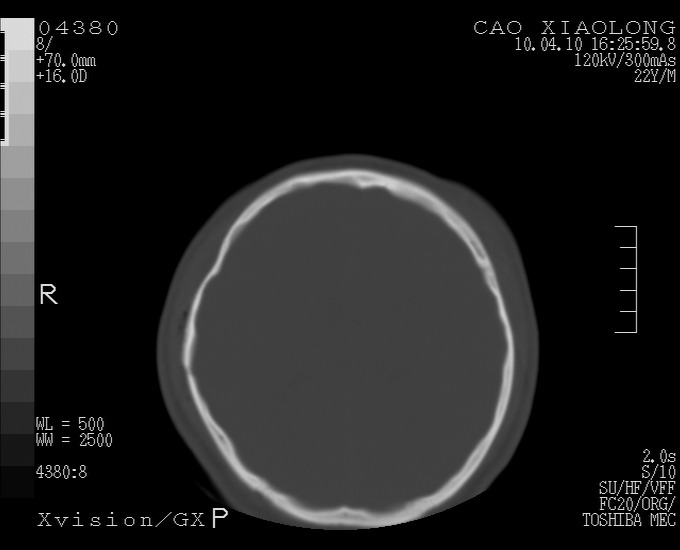

以下是引用随光逐影在2010-4-11 11:00:00的发言:[br]1)左侧额颞顶部硬膜下血肿。2)蛛网膜下腔出血。3)右侧颞顶部颅骨线形骨折。[br][br]20小时后复查:左侧额颞叶脑挫裂伤;左侧额颞顶部硬膜下血肿及蛛网膜下腔出血有吸收表现;右侧颞顶部颅骨线形骨折。[br]